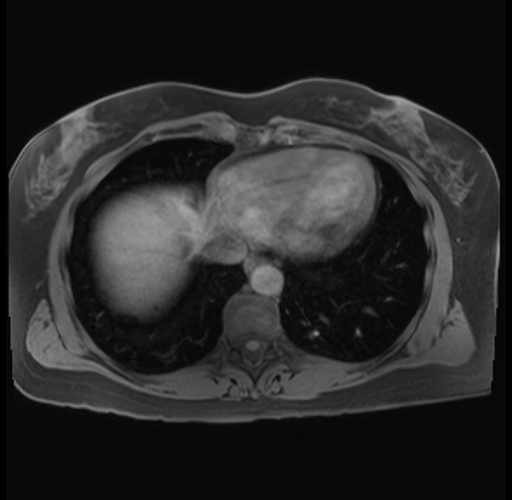

Imaging Analysis

Look through the patient's CT scan to identify any areas of concern for the necessary procedure.

Based on your CT findings, which issue(s) are present and would give reason for "planned slowing down moment(s)" in this case?

Considering a standard distal pancreatectomy procedure, what step(s) of the operation would you do differently in this case?